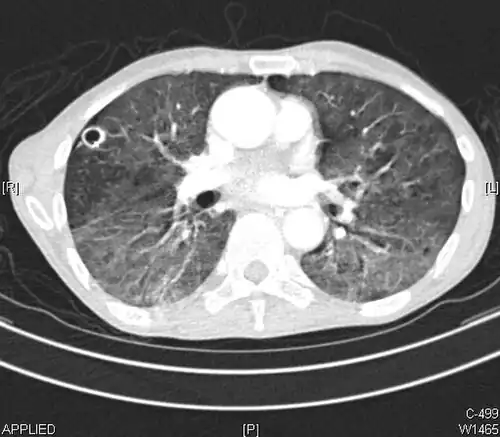

High-Resolution CT image in a patient with Pneumocystis pneumonia infection showing ground-glass opacities.

Inflammation and fibrosis can also cause diffuse GGOs. Pneumocystis pneumonia, an infection typically seen in immunocompromised (e.g. patients with AIDS) or immunosuppressed individuals, is a classic cause of diffuse GGOs. Many viral pneumonias and idiopathic interstitial pneumonias can also lead to a diffuse GGO pattern. Radiation pneumonitis, a side effect of pulmonary radiation therapy, can lead to pulmonary fibrosis and diffuse GGOs.[6]